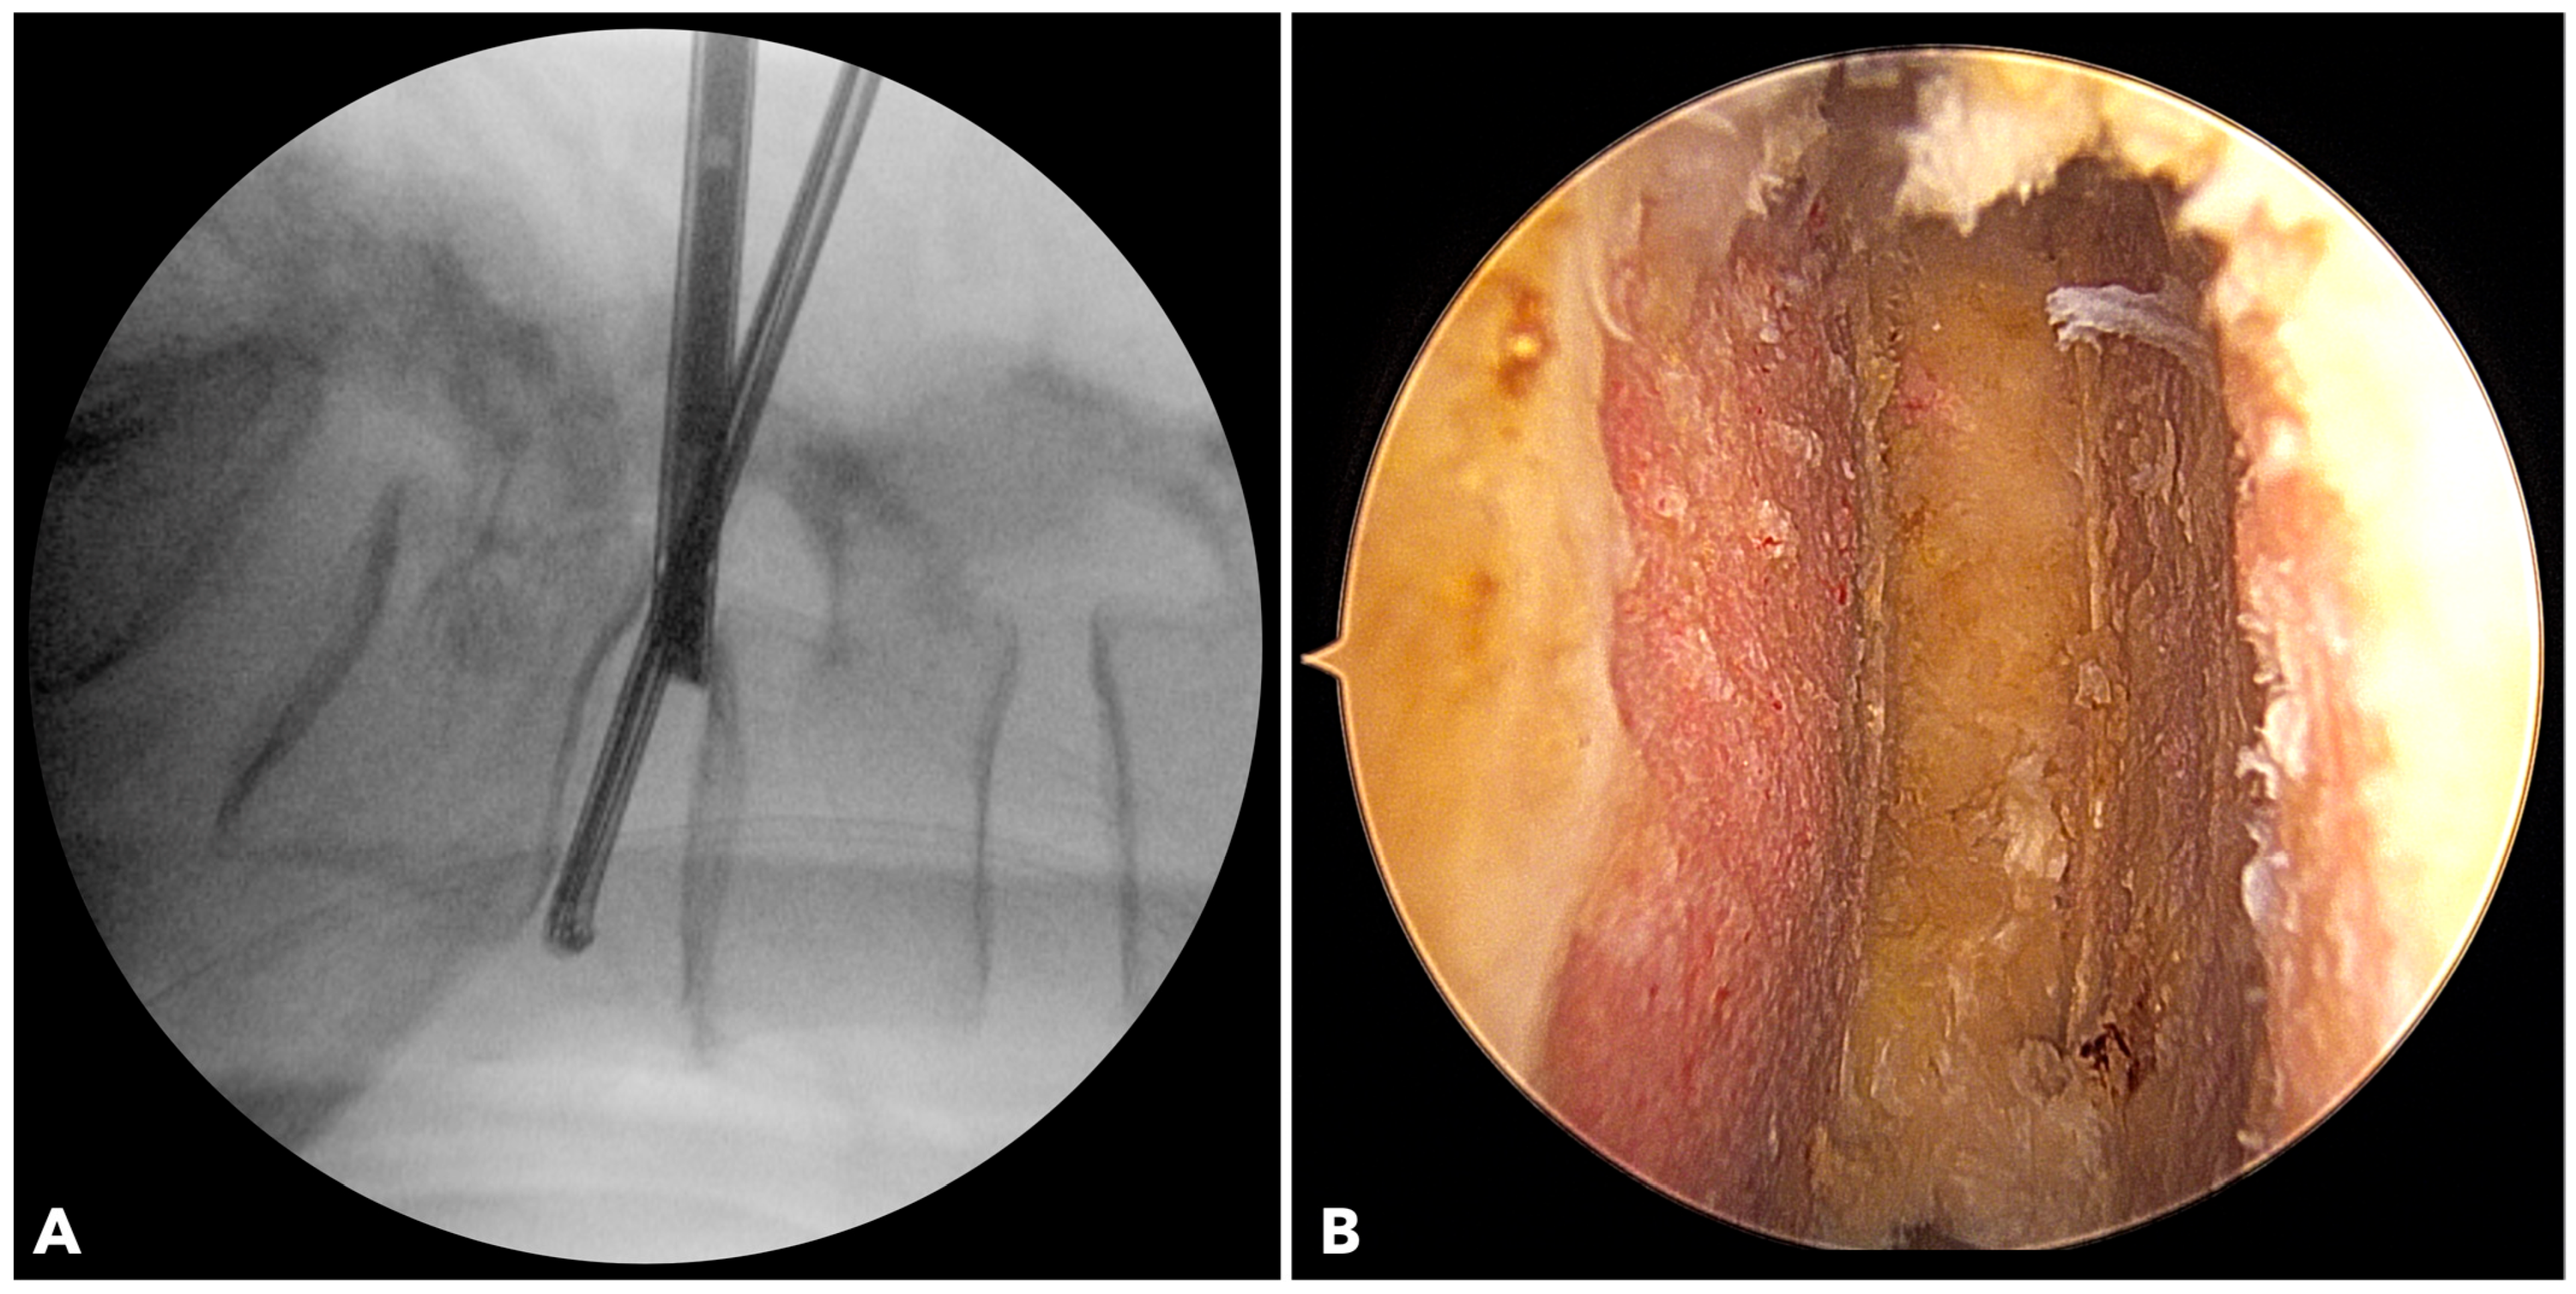

2.2.4. Disc Space Preparation

In BETLIF, direct endoscopic visualization enables radical discectomy while preserving the bony endplate. Sharp disc shavers and curettes are avoided in favor of blunt disc spreaders and specially designed endplate strippers. The endoscope is inserted into the disc space to ensure complete removal of the cartilaginous endplate (Figure 3). In MISTLIF, disc space preparation relies on tactile feedback via serial disc shavers and curettes, increasing the possibility of inadvertent endplate violation.

Figure 3. (A) The fluoroscope image shows the endoscope being inserted into the disc to evaluate the final results of disc space preparation. (B) The endoscopic photo verifies a perfect disc space preparation with no damage to the bony endplate.